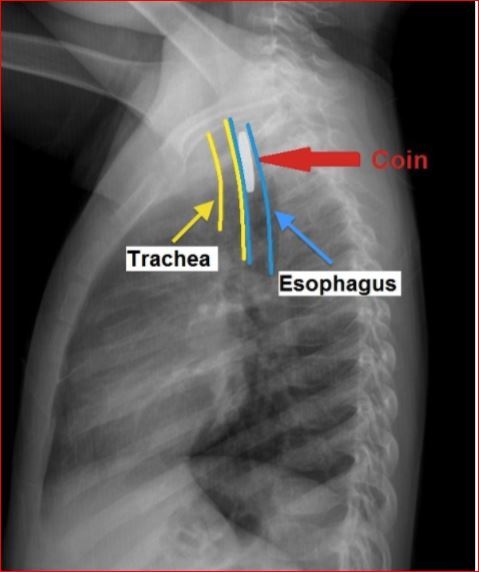

Do a 2-view (posterior anterior PA and later) neck xray and chest xray.

It confirms the location of the foreign body and distinguishes btwn a coin and battery (the latter can cause performation in just a few hours).

Coin is seen a homogenous object with a sharp, crisp edge; the bilaminar structure of a button battery causes a “double-ring” sign)

Child aspiration- battery versus coin?

Coin - homogenous with sharp crisp edge

Child aspiration (coin or battery)?

button battery

“double-ring” sign

WHen do you use emergency bronchoscopy versus endoscopy?

Emergency bronchoscopy would be appropriate for an airway foreign body causing respiratory distress.

This patient has no stridor, wheezing or respiratory distress and the lateral radiograph indicates the foreign body is in the esophagus rather than the airway.

In addition, an esophagel coin appears linear on lateral x-ray, a tracheal coin appears linear (project on end in the PA view) in the PA view.

Coin in esophagus versus trachea

an esphagel coin appears linear on lateral x-ray, a tracheal coin appears linear (project on end in the PA view) in the PA view.